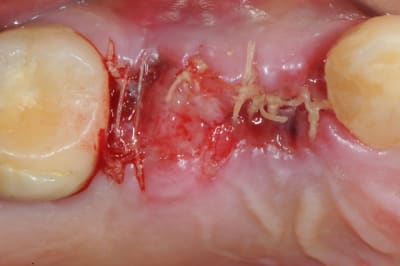

pour débuter ce post je propose un petit cas avec une ROG un comblement alvéolaire et un lambeau pédiculé pour fermer le site d'extraction.

au début incision supra crestal puis lambeau muco-périosté.

avec une simple lame 11 qui tranche le long de gencive palatine. évidemment c'est le plus dure à faire pour éviter de transpercer ou d'avoir d'un coté ou de l'autre une épaisseur trop faible.

toutefois je préfère que le lambeau soit pédiculé plutôt que libre. et vous ??